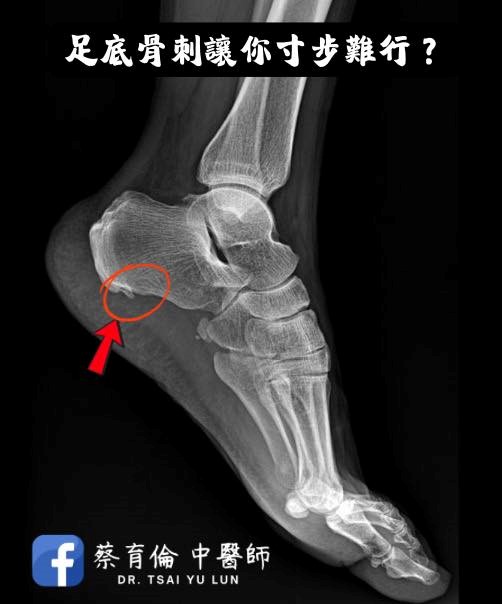

X光檢查顯示足跟骨刺, 曾服用止痛藥與熱敷治療, 但改善幅度有限。

足跟骨刺並非一根刺在戳腳, 而是足底筋膜長期受力後, 在筋膜與跟骨連接處形成的鈣化現象。

許多疼痛來源其實與筋膜緊繃與張力異常有關, 而不單純是骨刺本身。